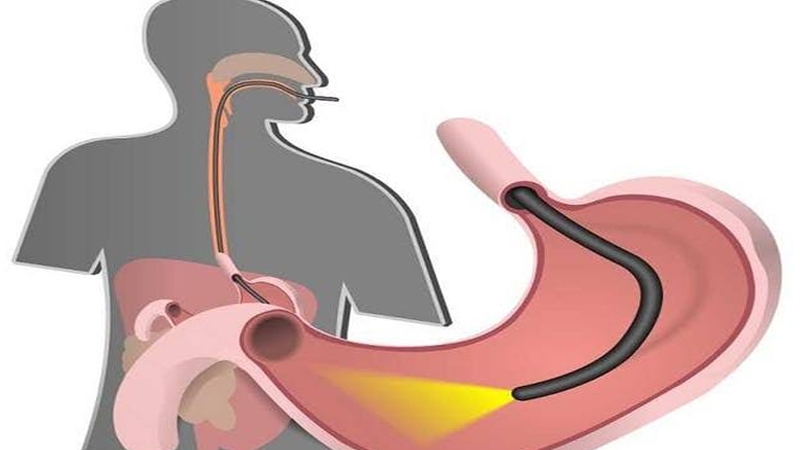

3 بذور طبيعية امضغها للتخلص من مشاكل المعدة

أمد/ الشعور بالثقل والحموضة والانتفاخ من المشكلات الهضمية الشائعة التي قد تحدث بعد تناول وجبة الغداء، وتختلف هذه الأعراض من شخص لآخر تبعًا لقدراته الهضمية وحالة بكتيريا الأمعاء لديه، وهناك علاجات طبيعية مدعومة علميًا تُساعد على الشعور بالراحة بعد الغداء، وفقًا لتقرير موقع Ndtv".

يُعد تناول ثلاثة أنواع من البذور، وهي الشمر والكراوية والكمون، ضروريًا للتخفيف من اضطرابات الهضم التي تحدث بعد الغداء، ويُفضل تناول هذه البذور نيئة أو محمصة مع مضغها قليلًا، حتى تُطلق مركباتها الطبيعية في الفم ويتم امتصاصها عبر اللعاب، ولكل نوع من هذه البذور، دور مُحدد في تحسين صحة الأمعاء.

يميل الهضم إلى التباطؤ بشكل طبيعي بعد الغداء، عندما يتناول الناس وجبات كبيرة تحتوي على الكثير من الدهون أو الكثير من الكربوهيدرات المكررة، وعندها تميل الأمعاء إلى مواجهة صعوبة في تحريك الطعام لامتصاص العناصر الغذائية، وكذلك انخفاض نشاط الإنزيمات، مما يؤثر على طريقة الهضم في الجسم بعد تناول الطعام.

تشتهر بذور الشمر بخصائصها الطاردة للغازات، مما يعني أنها تساعد على تقليل الغازات والانتفاخ، فهي تحتوي على مركبات مثل الأنيثول، التي تعمل على إرخاء الجهاز الهضمي وتعزيز عملية الهضم، كما أن مضغ بذور الشمر بعد الوجبات يمكن أن يحفز إفراز اللعاب، وهي الخطوة الأولى في عملية الهضم السليم.

بذور الكراوية فعالة بشكل خاص للأشخاص الذين يعانون من عسر الهضم أو الشعور بالثقل بعد تناول الطعام، فهي تحتوي على الثيمول، وهو مركب يعزز إفراز الإنزيمات المعدية، وهذا يساعد على هضم الطعام بكفاءة أكبر ويمنع مشاكل مثل الحموضة والغازات وعدم الراحة في البطن، وتُعد بذور الكراوية مفيدة بشكل خاص بعد تناول الوجبات الدسمة أو الثقيلة.

تلعب بذور الكمون دورًا حاسمًا في تحسين كفاءة الجهاز الهضمي بشكل عام، فهي تحفز البنكرياس على إفراز الإنزيمات الهاضمة، مما يساعد على امتصاص العناصر الغذائية بشكل أفضل، كما يُعرف الكمون بقدرته على تقليل الالتهابات في الأمعاء، ويمكن أن يساعد في تنظيم حركة الأمعاء.